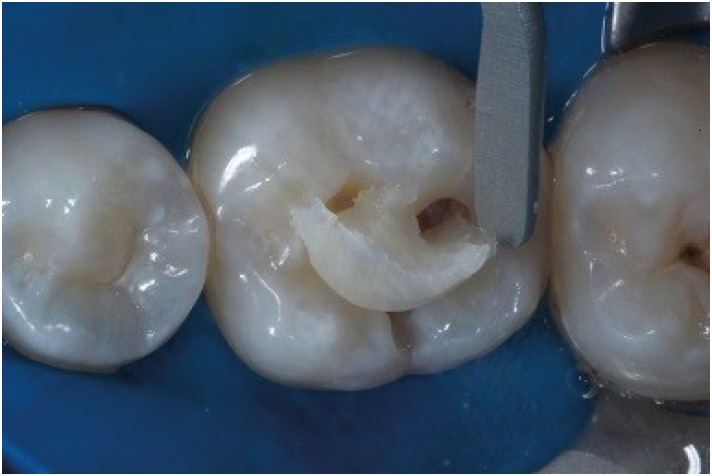

The patient sought the Department of Dentistry of the Federal University of Sergipe (Brazil) for a general oral health assessment. The clinical examination showed a carious lesion on the right mandibular first molar, and the restorative treatment plan was determined based on the clinical and radiographic findings (Figure 1). In order to establish an improved oral and aesthetic rehabilitation, an acrylic resin matrix was produced due to the preservation of the dental anatomy itself (Figure 2). For such production, an insulator was applied with the help of a microbrush on the tooth surface. After manipulating the powder/liquid of the acrylic resin (Jet Classico, Sao Paulo, SP, Brazil) in a paladon recipient (Golgran, Sao Caetano do Sul, SP, Brazil) with a spatula, the resin was applied on the occlusal surface of the tooth. After fixation, the resin was removed and maintained in water to prevent distortion, while the other procedures were performed.

Figure 1

Occlusal view of carious lesion.

Initially, the verification of occlusal contacts was performed, as well as prophylaxis with pumice stone and water, at low rotation with Robbinson brush (Microdont, Sao Paulo, SP, Brazil). The enamel was accessed with a high-speed 1011 spherical diamond bur (KG Sorensen, São Paulo, SP, Brazil) and the carious tissue was removed with a low-speed #4 (KG Sorensen) spherical carbide bur (Figure 3). Continuing with the restorative process, etching was performed with 37% phosphoric acid (Condac – FGM, Joinville, SC, Brazil) for 30 seconds in enamel and 15 seconds in dentin followed by cleaning with water for double the time. The dentin was dried with sterile absorbent paper, and the application and photopolymerization of the adhesive system were done (Single Bond; 3M ESPE, Campinas, SP, Brazil) using LED light (Radii-Cal; SDI, Victoria, Australia). The acrylic resin matrix was removed from the recipient with water and dried with sterile gauze and air blast. A single increment of bulk-fill resin composite (Aura Bulk Fill; SDI) was placed in the cavity with a resin spatula, and the matrix was positioned on the tooth with light pressure, followed by a 20-second polymerization with and without the matrix (Figures 4, 5 and 6). After assessing the occlusal contact, the excesses were removed with finishing points and burs. Twenty-four hours after completing the restoration, it was finished and polished with rubbers Optimize (TDV, Pomerode, SC, Brazil) (Figure 7).

Figure 3

Class I cavity prepared with spherical bur.